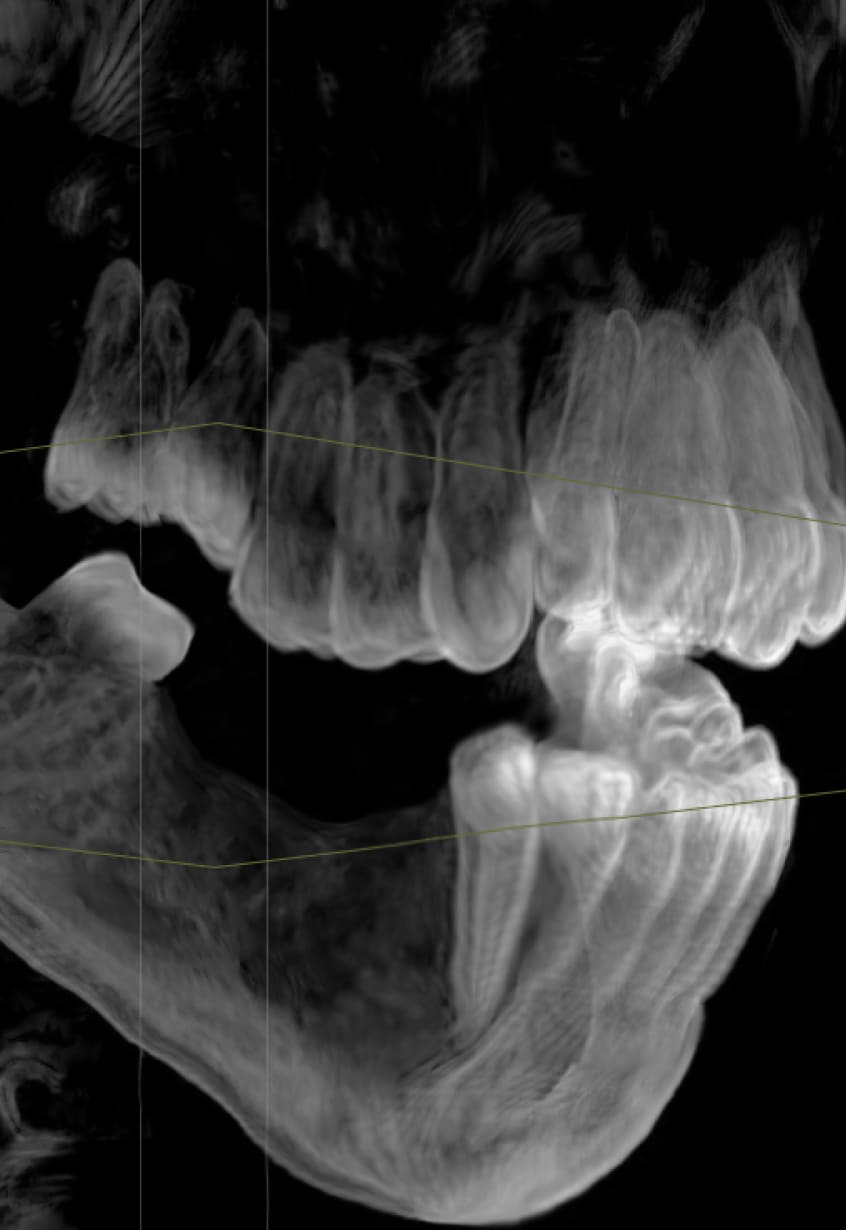

По 3D-модели врач определит положение будущих имплантов и составит план операции. В этом поможет искусственный интеллект, обученный на 50 000 случаев.

Ортопед изучит снимки и состояние вашего здоровья. Назначит консультацию с профильными специалистами.

Консультация и план

Комплексная 3D диагностика

Осмотр имплантолога и ортопеда